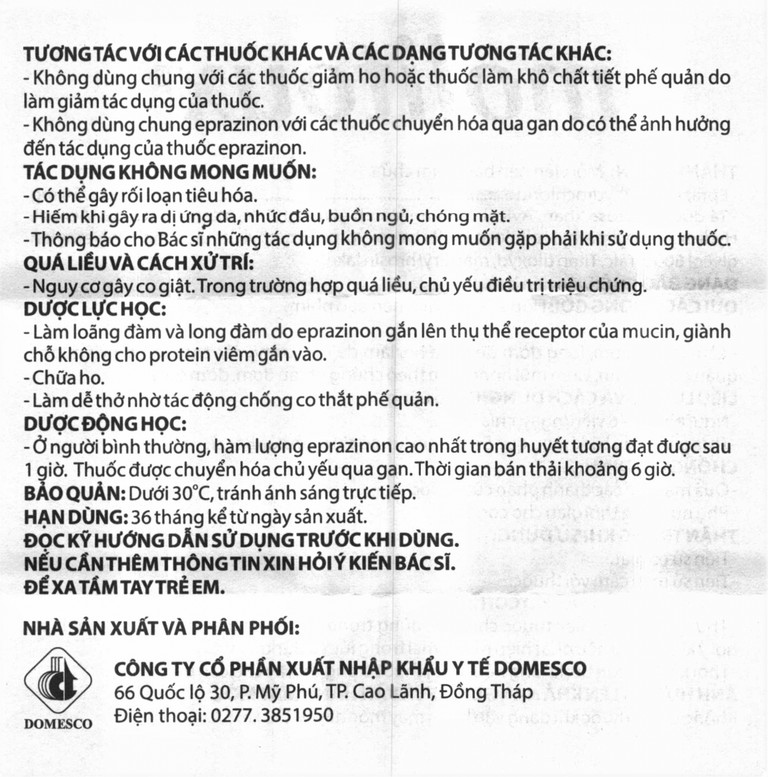

Dược lực học

Làm loãng đàm và long đàm do eprazinon gắn lên thụ thể receptor của mucin, giành chỗ không cho protein viêm gắn vào.

Chữa ho.

Làm dễ thở nhờ tác động chống co thắt phế quản.

Dược động học

Ở người bình thường, hàm lượng eprazinon cao nhất trong huyết tương đạt được sau 1 giờ. Thuốc được chuyển hóa chủ yếu qua gan. Thời gian bán thải khoảng 6 giờ.

Có thể gây rối loạn tiêu hóa.

Hiếm khi gây ra dị ứng da, nhức đầu, buồn ngủ, chóng mặt.

Thông báo cho bác sĩ những tác dụng không mong muốn gặp phải khi sử dụng thuốc.

Tương tác thuốc

Không dùng chung với các thuốc giảm ho hoặc thuốc làm khô chất tiết phế quản do làm giảm tác dụng của thuốc.

Không dùng chung eprazinon với các thuốc chuyển hóa qua gan do có thể ảnh hưởng đến tác dụng của thuốc eprazinon.

Bảo quản

Dưới 30°C, tránh ánh sáng trực tiếp.